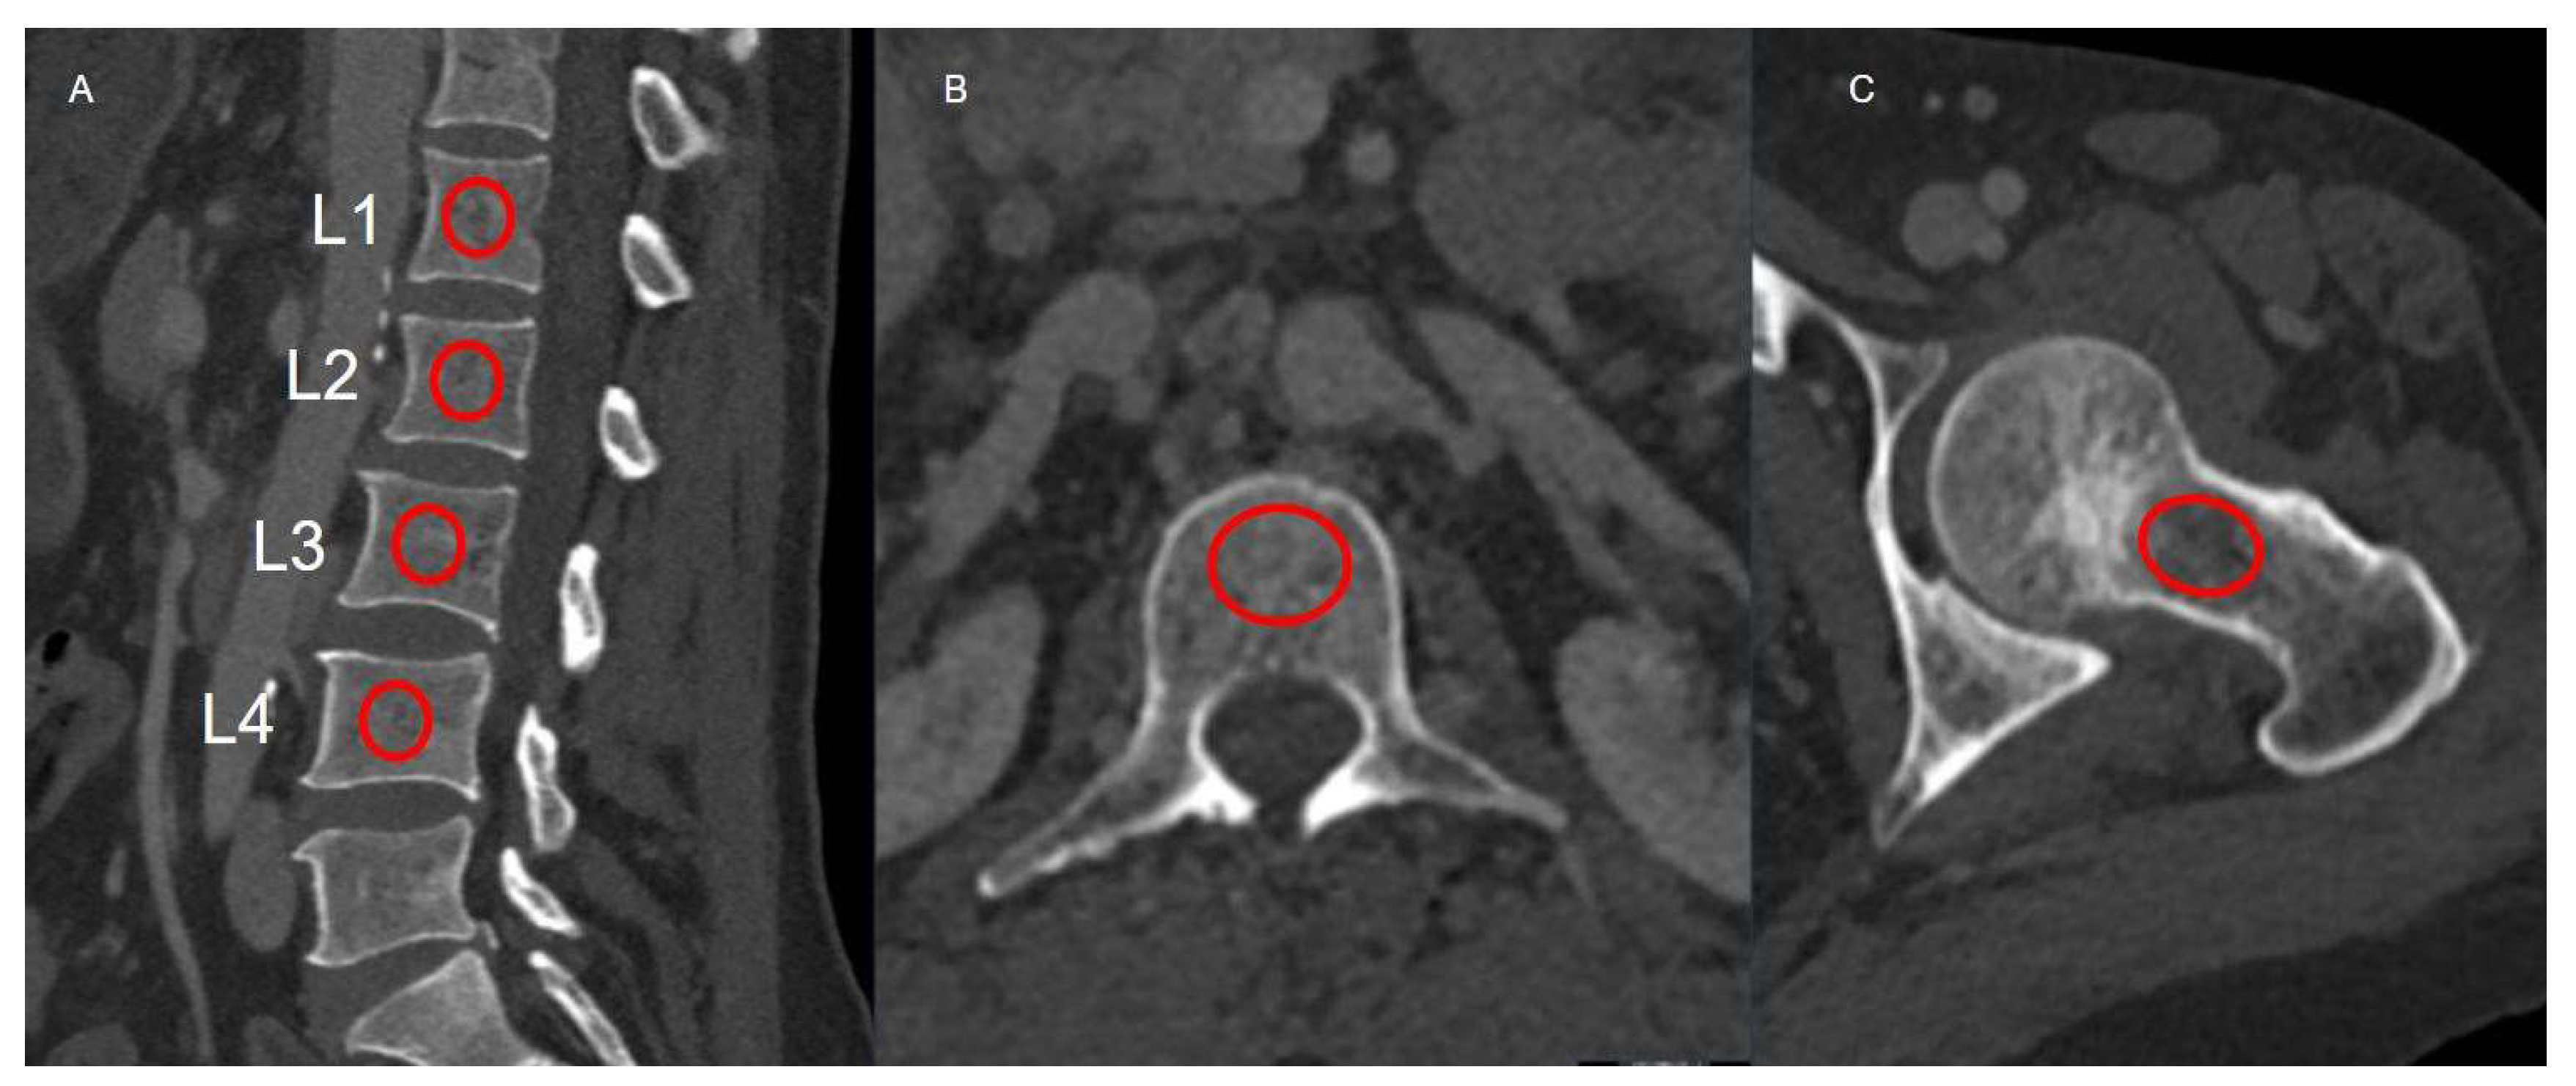

2.2. CT Acquisition Protocol and HU Measurements